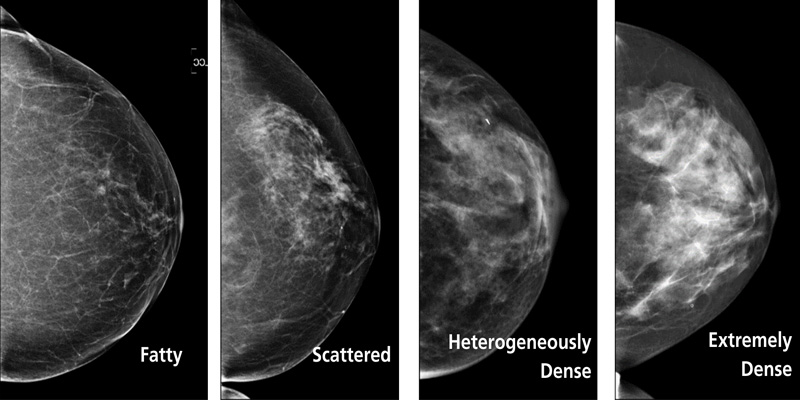

Phân loại mật độ vú theo hệ thống BI-RADS

Để chuẩn hóa đánh giá, bác sĩ sử dụng hệ thống BI-RADS nhằm phân loại mật độ mô vú trên nhũ ảnh:

- BI-RADS A: Vú chủ yếu là mô mỡ, khả năng phát hiện tổn thương cao

- BI-RADS B: Vẫn là mô mỡ chiếm ưu thế, xen kẽ một số vùng mô tuyến

- BI-RADS C: Mô vú có mật độ không đồng nhất, bắt đầu gây khó khăn trong phát hiện khối nhỏ

- BI-RADS D: Mô vú rất dày, mô tuyến và mô liên kết chiếm phần lớn, nguy cơ che lấp tổn thương cao

Những người thuộc nhóm C và D thường cần theo dõi kỹ hơn hoặc bổ sung thêm phương pháp chẩn đoán khác.